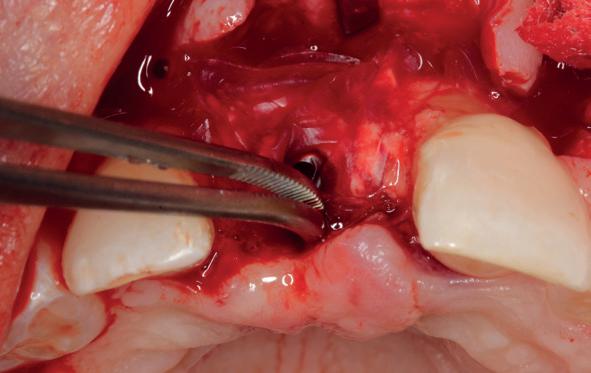

Implantologische behandelingen in het esthetische front vragen meer dan technische vaardigheid alleen. Ze vragen om overzicht, timing, vertrouwen en een team dat als vanzelf samenwerkt onder druk. Juist bij complexe casussen, waarin angst, infectie en hoge esthetische verwachtingen samenkomen, wordt zichtbaar hoe bepalend de rol van de tandartsassistent is.

Deze casus beschrijft een uitgebreide immediate implantaatbehandeling bij een patiënt die door meerdere collega’s werd geweigerd. Niet omdat de mogelijkheden ontbraken, maar omdat de complexiteit vroeg om een perfect afgestemde samenwerking. Het verhaal laat zien hoe de assistent in zo’n traject veel meer is dan een uitvoerende kracht of “mal”, maar een dynamische surgical guide die het proces mede stuurt, bewaakt en mogelijk maakt.De patiënt: wanneer alles samenkomt

Na het klinische onderzoek volgde het röntgenologisch traject. De CBCT liet precies zien wat we al vreesden: een front waarin het bot onregelmatig was, duidelijke radiolucenties rond de pijlers en een infectiegebied dat zich onder vrijwel de gehele brug had verspreid. Tegelijkertijd was er ook potentie. Net voldoende botstructuur om immediate implantaatplaatsing te overwegen, mits alles perfect gepland zou worden.

Die planning gebeurde in R2Gate, niet als technologische “fetish”, maar als noodzakelijk hulpmiddel. Met behulp van intra-orale scans, foto’s en CBCT-data bouwden we stap voor stap het verhaal van haar mond op. Wat was er misgegaan, wat was er nog mogelijk en hoe konden we haar bestaande brug kopiëren en verbeteren tot een tijdelijke oplossing die dezelfde dag functioneel zou zijn.

Terwijl ik door de digitale lagen bladerde, werkte mijn assistent rustig naast me. Geen grootse momenten, geen spektakel, maar die vertrouwde samenwerking. Ze controleerde of alle componenten besteld waren, keek mee naar de scans en stelde af en toe een eenvoudige vraag die precies raak was. “Kunnen we niet ook een uitneembare constructie als back-up laten maken, voor het geval de initiële

5. Klinische foto direct na verwijdering van de brug.